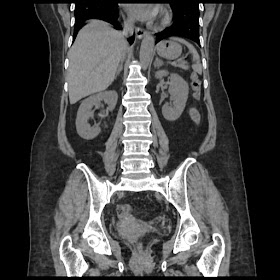

A CT abdomen revealed a left adrenal cortical tumor.

Her abdominal X-ray also reveals a right renal stone although she never complained of renal colic.

Clinician advised against surgery because she was not in pain. Her TSH is normal. A CT abdomen revealed a left adrenal cortical tumor. Diagnosis of pri. aldosteronism was made. Patient is hypertensive since 1995 since her second childbirth. Now BP is normal with medication. She is nondiabetic. Pt. advised to report her Ca2+ and K+ lvl. monthly. Pt. acq. the habit of eating paan (beetle leaf) from her mother in 2011 when she came to stay with her. Used to eat 3-4 paans a day. Stopped in 2013 after Dr. advised against it.

PATIENT'S HISTORY: The patient is a 60-year-old housewife. In 2013, she had an episode of probable stroke followed by nausea, vomiting, diarrhea, weakness, fatigue with loss of appetite, and insomnia. Her legs felt numb. She lost sensation around neck. Had to be admitted to a nursing home. Diagnosis of hypocalcemia and hypokalemia was made. Got discharged after 5 days when k+ and Ca2+ lvl. returned to normal via i.v infusion. For 2 yrs she was fine. In 2015, due to diarrhea and fatigue she got admitted to a Nursing home and stayed there for 7 days. Ca2+ and K+ lvl. was falling, so restored via i.v infusion. This time hypernatremia was also detected. Discharged after her conditions improved. But 2 days later, again due to severe diarrhea had to be admitted to a Nursing home for 19 days. During her stay USG of abdomen, colposcopy and chest X-ray was done. USG detected a large renal calculus measuring 22mm in rt. kidney. Sx was recommended. Pt went to Bhopal for a second opinion.